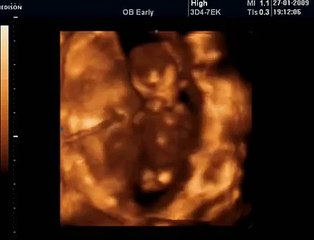

www.cemturan.combr www.dr-cemturan.combr www.jinekolojikonkoloji-istanbul.combr www.perinatoloji-istanbul.combr Hamilelikte renkli Doppler ultrason niçin yapılır? Bebek renkli mi görülür yoksa damarları görmek için mi renkli Doppler yapılır? Prof. Dr. Cem Turan'dan izleyin. Renklli doppler ultrason ile en çok incelenen damar bebeğin göbek kordonundaki damarlardır (umblikal damarlar). Bunun dışında rahim damarları, beyin damarları, kalp damarları gibi çeşitli damarlar incelenebilir. Özellikle rahim içerisinde gelişme geriliği (iugr) şüphesi olan bebeklerde, anomali varlığında, kalp ritm bozukluğu veya kardiyak anomali varlığında, yüksek tansiyon hastalarında yapılır. Her gebelikte rutin olarak yapılan bir inceleme değildir.